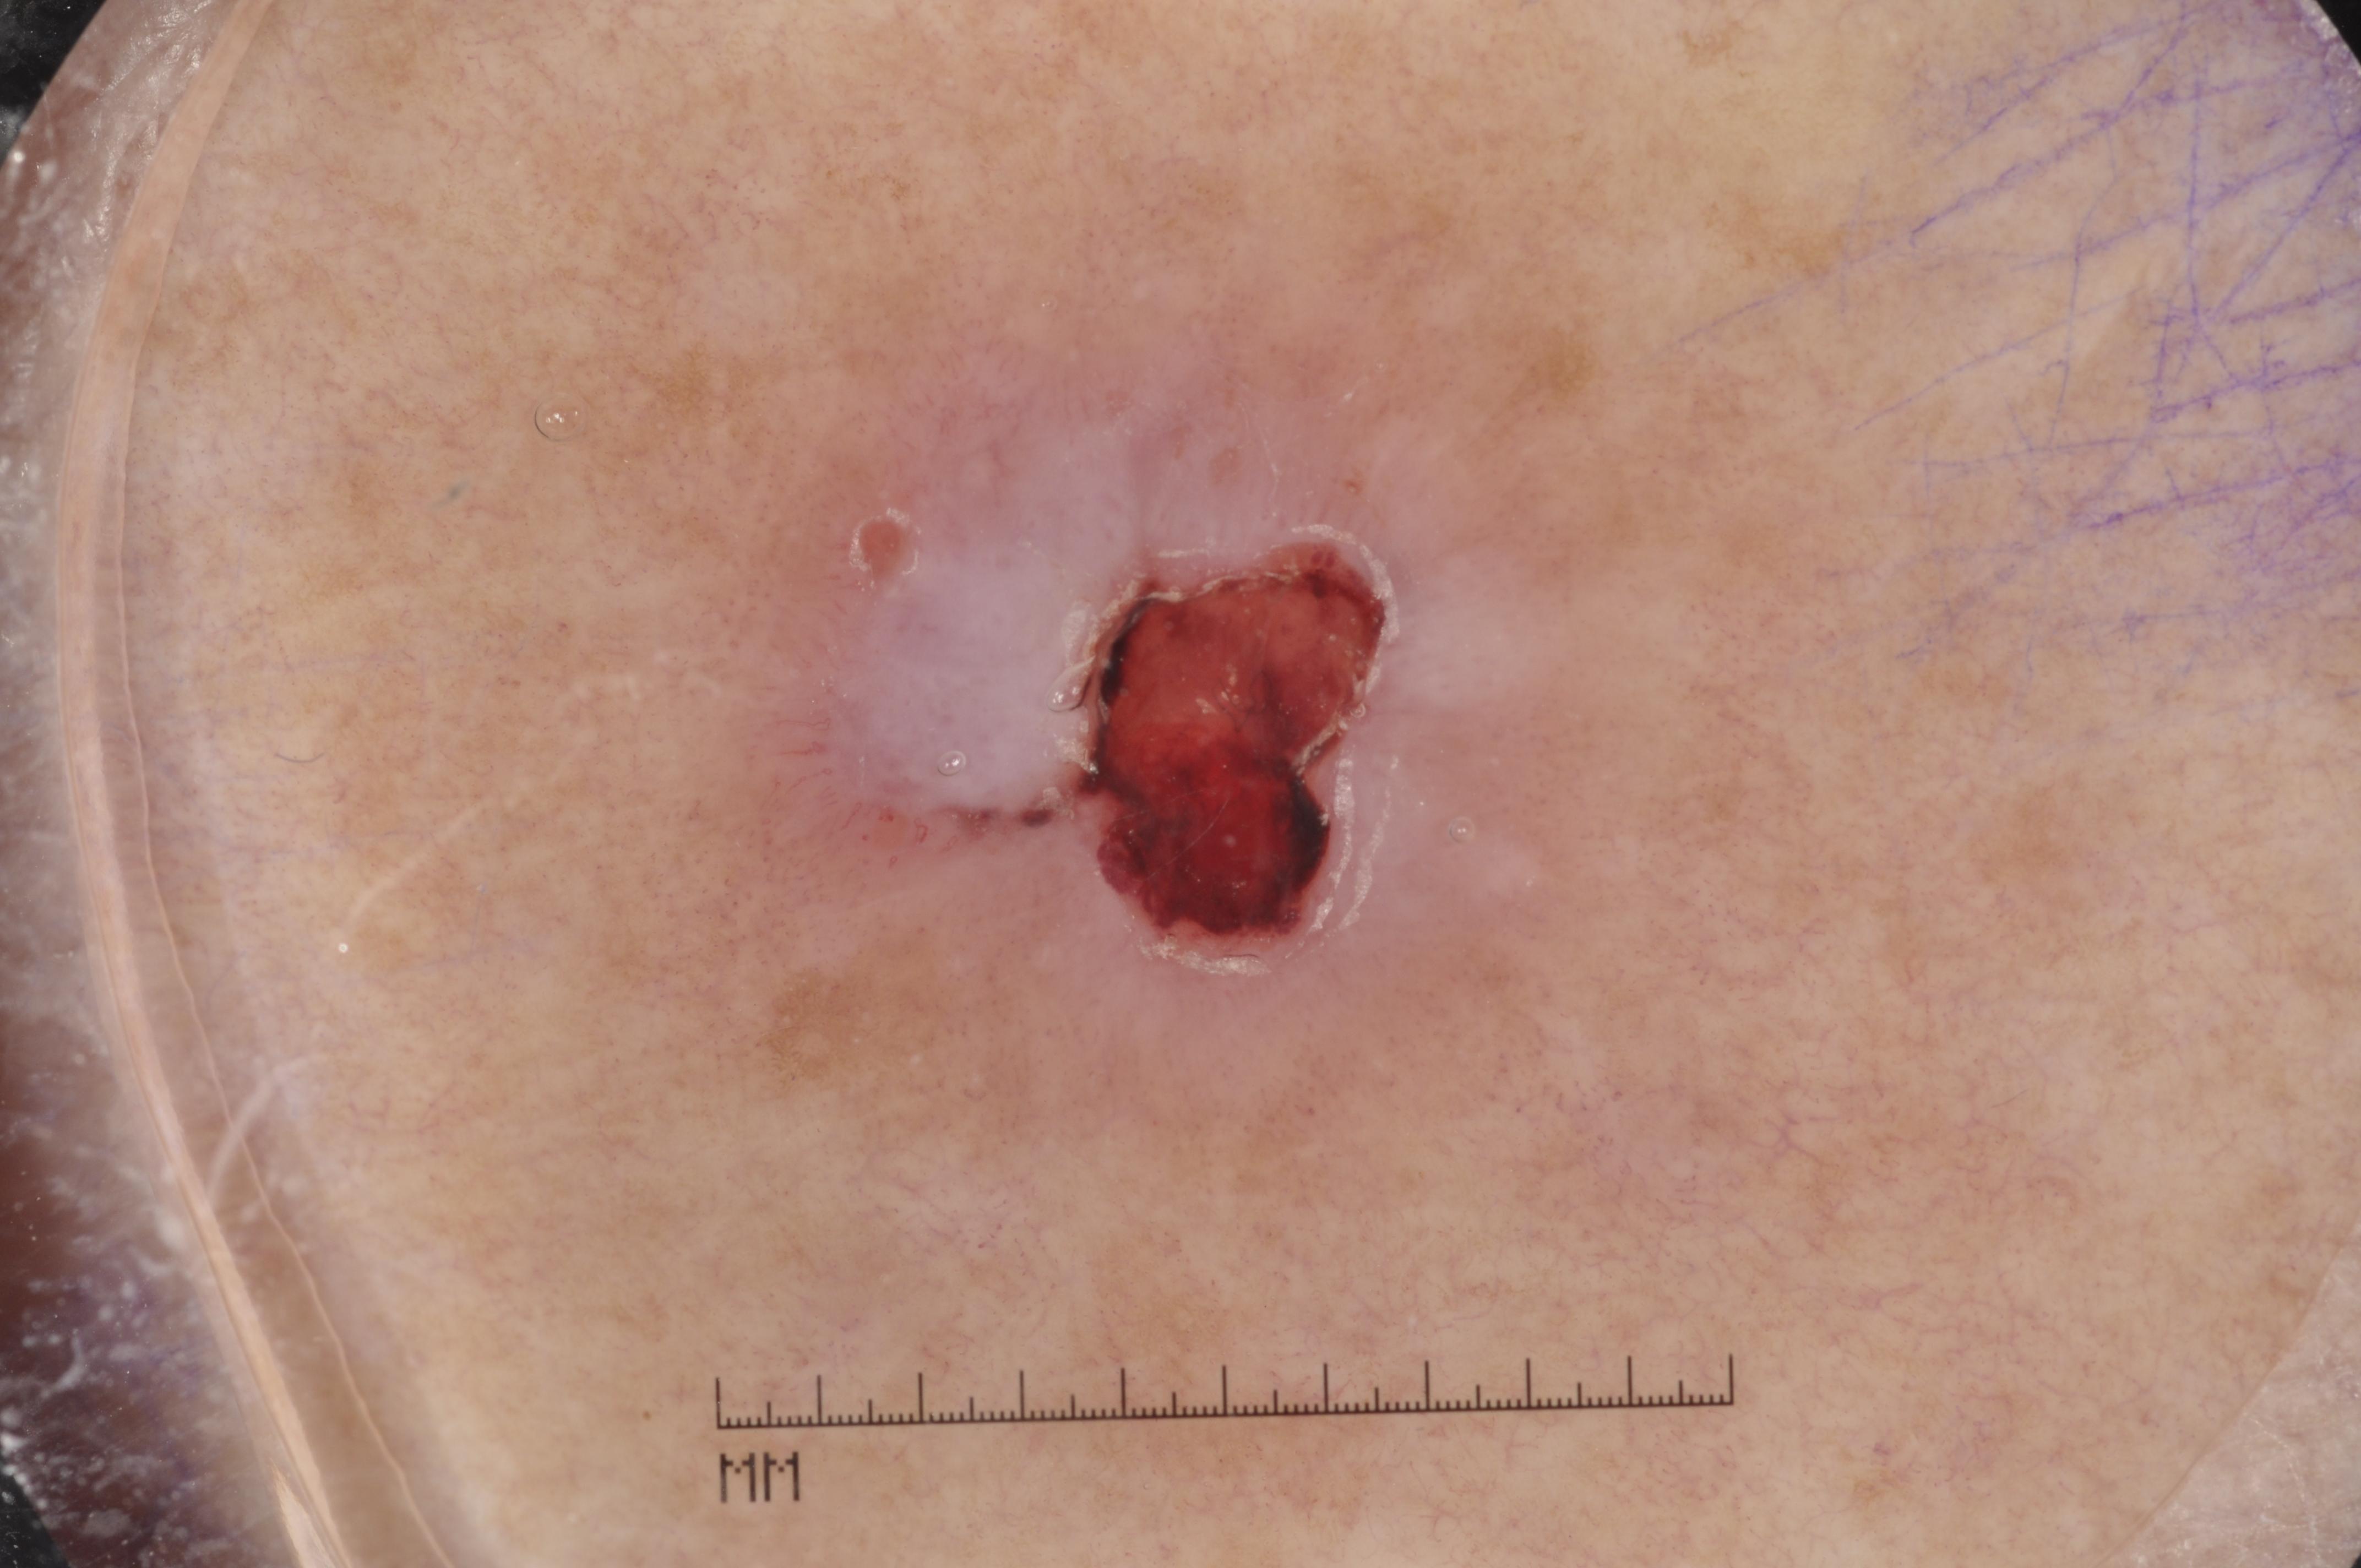

{

"age_approx": 70,

"anatom_site_general": "head/neck",

"concomitant_biopsy": true,

"dermoscopic_type": "contact non-polarized",

"diagnosis_1": "Malignant",

"diagnosis_2": "Malignant adnexal epithelial proliferations - Follicular",

"diagnosis_3": "Basal cell carcinoma",

"diagnosis_confirm_type": "histopathology",

"image_type": "dermoscopic",

"lesion_id": "IL_0235161",

"melanocytic": false,

"sex": "male"

}